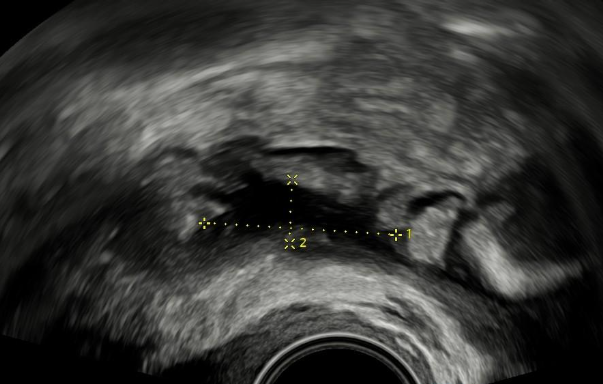

Endometrióza tlustého střeva.